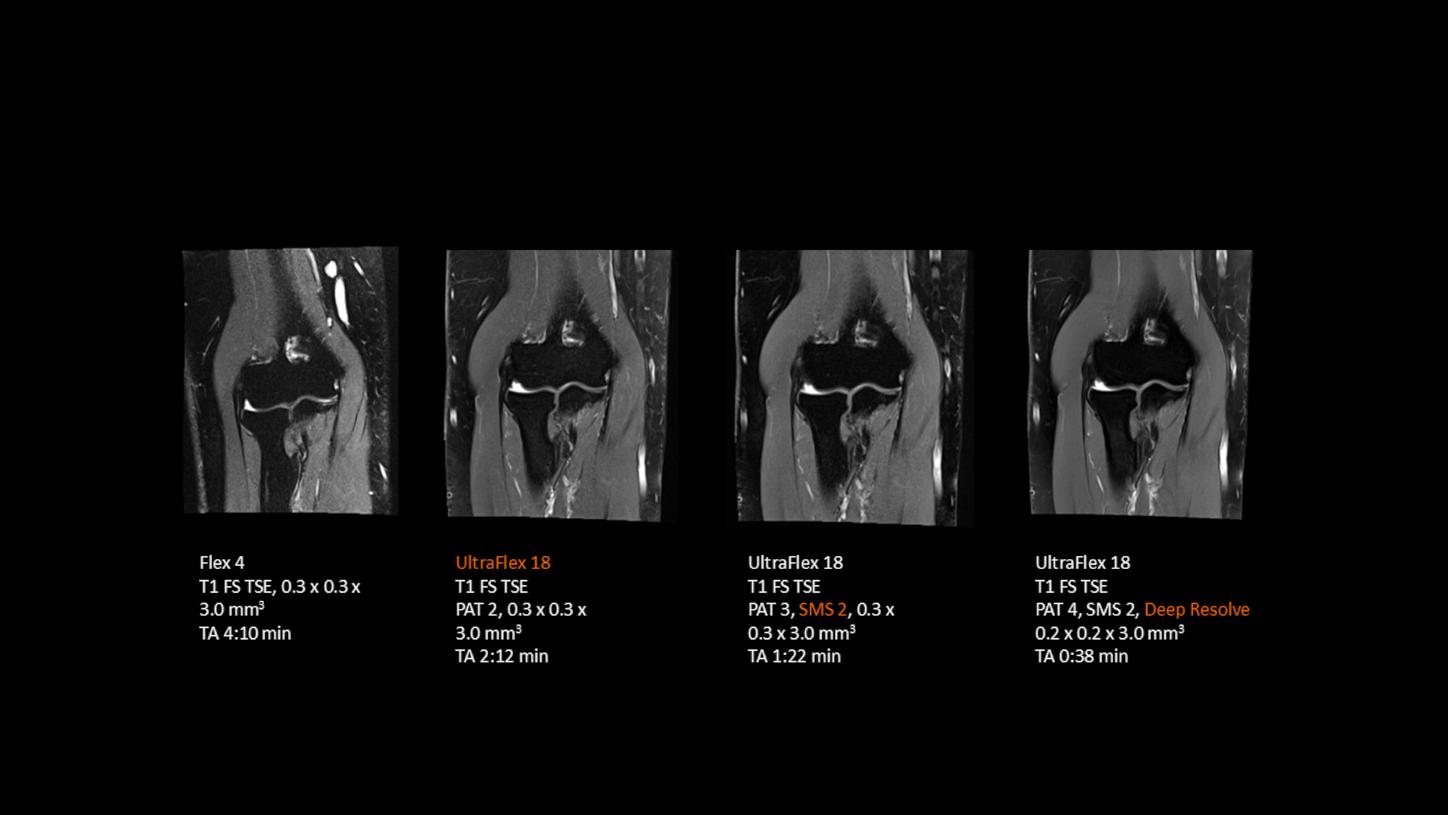

Deep Resolve is at the forefront of the revolution in MRI acceleration. Deep Resolve delivers our fastest MRI, delivering images of extraordinary clarity, higher clinical productivity, and a better patient experience.